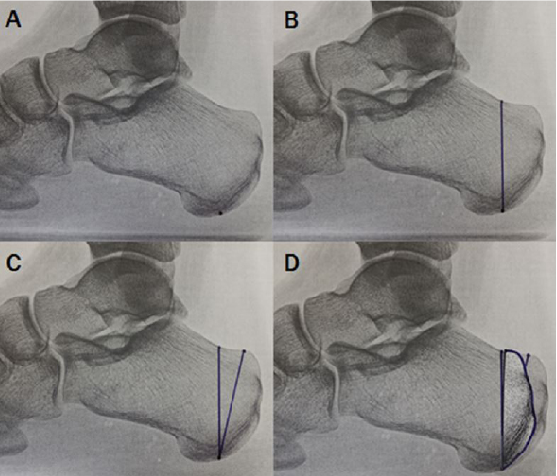

Preoperative templates are useful in determining the size of wedge resection with the Keck and Kelly dorsally-based wedge resection. The posterior cut should have a dorsal exit point just anterior to the Achilles tendon. The inferior apex of the wedge is posterior to the weightbearing area of the plantar calcaneal tuberosity. The anterior cut should be vertical on the lateral weightbearing image. A 7 to 9 mm wedge is generally needed to gain adequate correction depending on the individual anatomy of the calcaneus. One would place a linear incision on the lateral heel directly over the osteotomy site and intraoperative fluoroscopy-guided incision planning is useful in this regard. The surgeon can make a full thickness incision down to bone as the sural nerve and peroneal tendons are well anterior with this approach. Perform blunt dissection superiorly near the Achilles tendon and free the periosteum from the lateral and dorsal aspects of the calcaneus. This enables the surgeon to gain only enough exposure for the planned osteotomy.

One can employ intraoperative fluoroscopy to confirm that osteotomy exit points match the template. The surgeon can use an osteotomy guide over guide pins to facilitate cuts that are parallel from medial to lateral yet converge at the desired location at the plantar cortex. One would leave the plantar cortex intact for the final greenstick fracture. The strong plantar soft tissues act as a plantar hinge and prevent proximal migration of the posterior fragment in the sagittal plane. Dorsiflexing the foot manually allows the intact Achilles to compress the osteotomy. We used two cannulated cancellous screws to fixate the osteotomy.